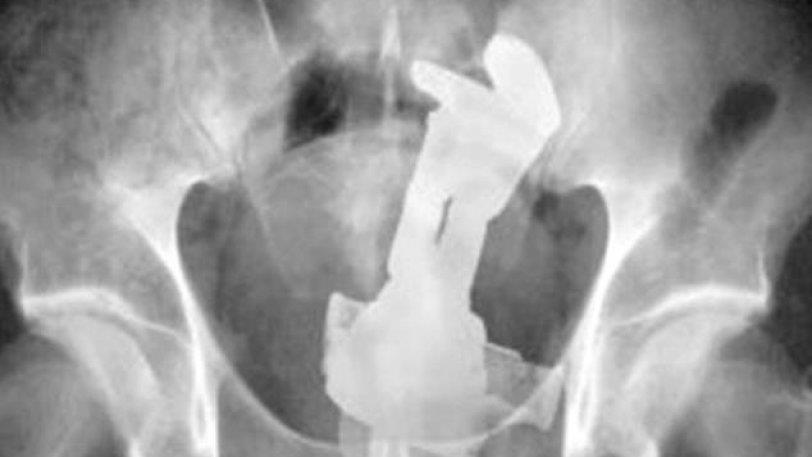

7. Ένα ερωτικό βοήθημα